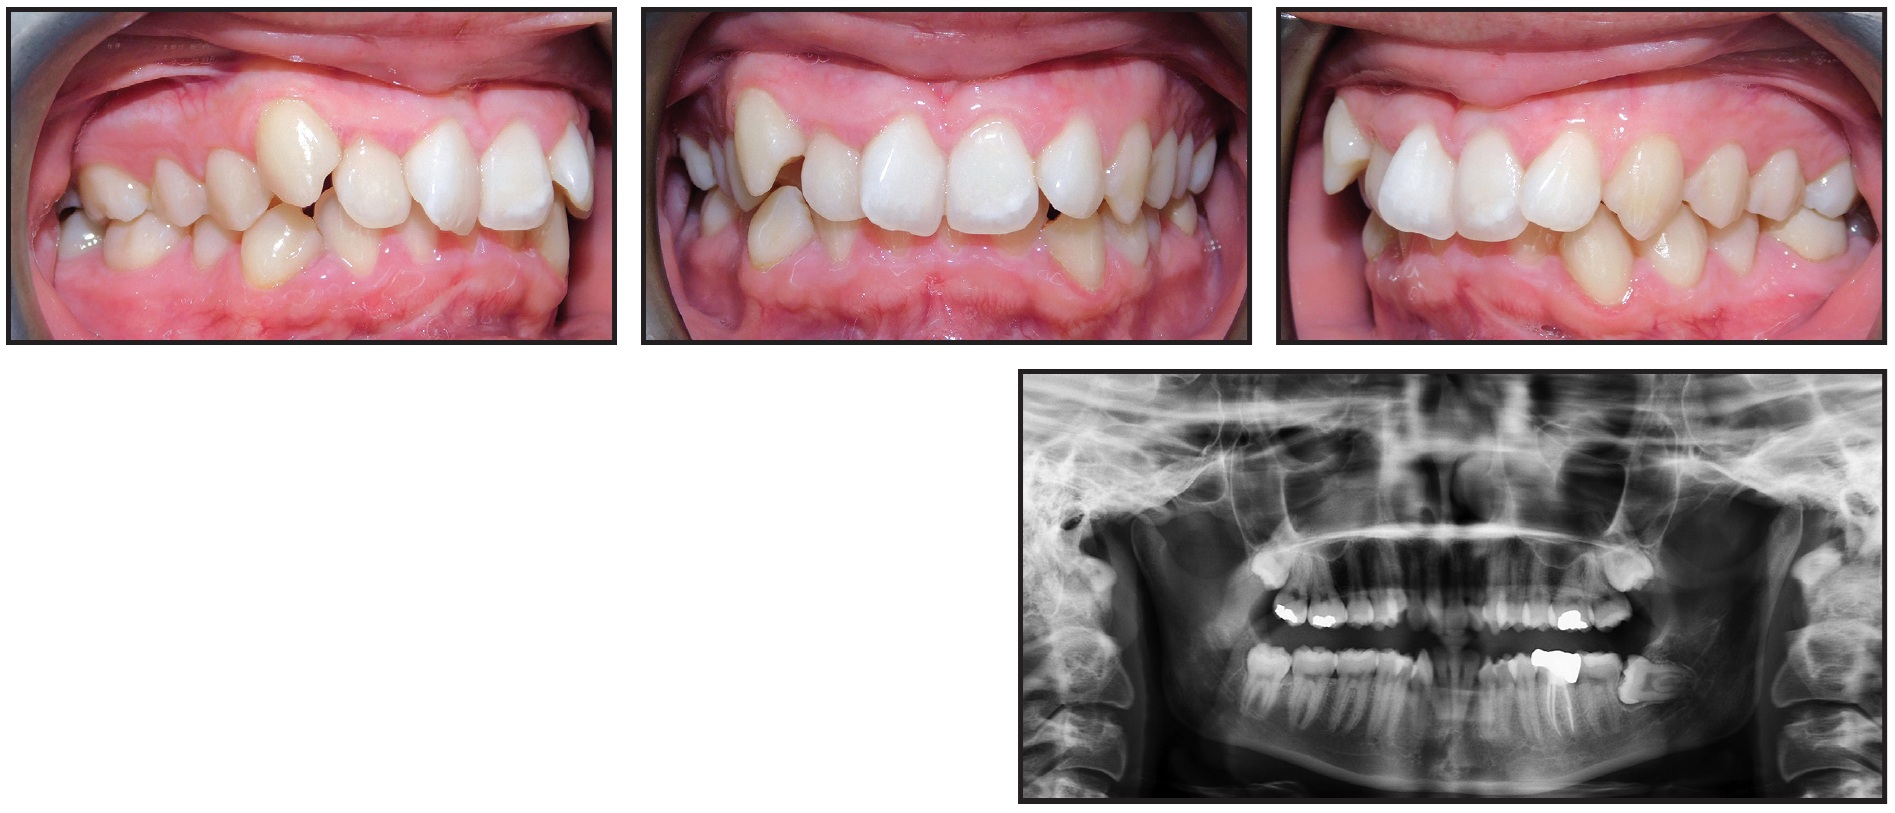

In this case, a 21-year-old female presented with a Class I malocclusion, excessive overjet, deep overbite, severe crowding, and bimaxillary protrusion (Fig. 8).

Fig. 8 21-year-old female patient with Class I malocclusion, excessive overjet, deep overbite, severe crowding, and bimaxillary protrusion before treatment.

We planned four premolar extractions, maximum anchorage, leveling of the curve of Spee, and incisor retraction. In the initial treatment design, I made the mistake of not adding attachments to the lower lateral incisors (Fig. 9).

Fig. 9 After 11 months of treatment and initial set of aligners, showing inadequate torque control of lower incisors and posterior open bite.

For the refinement stage, I focused on final space closure, root parallelism at the extraction sites, and finishing of the occlusion to close the posterior open bite. Although I added attachments to the lower lateral incisors for the refinement, the overall distal root angulation as designed and expressed in treatment was insufficient (Fig. 10). (The situation was exacerbated when one of the attachments debonded.)

Fig. 10 After one year of refinement, showing insufficient distal root angulation of lower incisors.

Regular monitoring of any orthodontic treatment is of paramount importance. Periodic assessments allow timely adjustments and interventions, ensuring proper root control. Before ordering additional aligners, I recommend that the appropriate root angulation be confirmed with a progress panoramic radiograph. Consider adding new attachments and distal root angulation in the digital setup if the issue persists or if you missed it in the initial treatment design. Such adjuncts to treatment can be applied in any challenging cases, including fixed segmental mechanics.